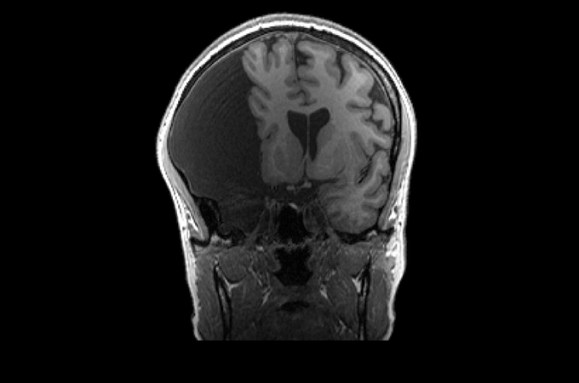

Elyse G. found out she lacked most of her left temporal lobe when she was 25 years old. The brain region is typically crucial for speech and language — but until her brain was scanned (three views shown), no one knew Elyse was missing hers.

Looking at her brain scans is a different story. It’s as if someone has knocked over a bottle of ink. The darkness pools inside her skull near her left ear, a puddle of fuliginous black. Inside the splotch, there’s no white matter or gray matter, no blood vessels or tissue at all.

When Elyse and Fedorenko first met, Fedorenko was interested in how language areas wire up when a chunk of crucial tissue is missing. Her plan was to peek inside Elyse’s head using functional MRI, a technique that tracks blood flow in the brain. Functional MRI lets scientists see which parts of the brain are active while a person performs a specific task.

Elyse’s first scan with Fedorenko’s team revealed language activity in the right side of the brain, the team reported in 2022 in Neuropsychologia. Shifting functions to the right is one trick our brains use to deal with damage on the left, something other scientists have reported previously, Fedorenko says.